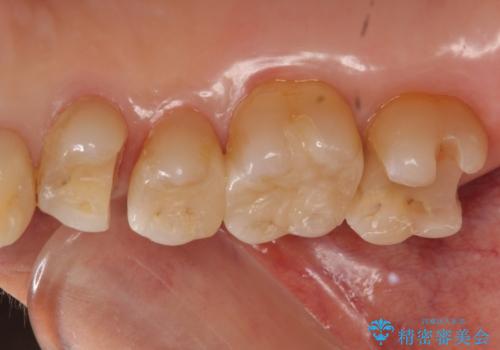

銀歯を白く 虫歯治療

- 虫歯治療を希望して来院。

保険適用の銀色のつめもののやり替えを行いました。

- 30.8万円(右上4567 emaxプレスインレー 7万円x4本)費用は治療当時の料金となります

自由診療のインレーの歯型には、シリコンを使用しています。また、処置時には8倍の拡大鏡を用いて、精密に治療しております。